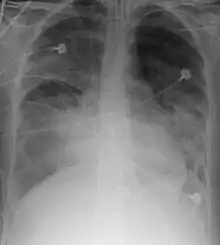

تصوير الصدر بالأشعة السينية

تصوير الصدر بالأشعة السينية هي الطريقة الأكثر شيوعًا المستخدمة للتشخيص ويمكن استخدامها لتأكيد التشخيص الذي تم إجراؤه باستخدام العلامات السريرية.[33] تظهر مناطق الحويصلات الهوائية الملتصقة ببعضها البعض بسبب الإصابة بيضاء في فيلم الأشعة السينية.[34][35][36] قد يؤدي تجمع الدم أو استرواح الصدر إلى حجب الكدمة في الصورة الشعاعية.[37]

على الرغم من أن التصوير الشعاعي للصدر يعد جزءًا هامًا من التشخيص[38]، إلا أنه غالبًا ما يكون غير حساسًا بما يكفي لاكتشاف الحالة مبكرًا بعد الإصابة. في ثلث الحالات، لا تظهر الكدمة الرئوية على أول تصوير لأشعة الصدر.[39] يستغرق الأمر ست ساعات تقريباً حتى تظهر المناطق البيضاء المميزة للكدمة الرئوية على الأشعة السينية. إذا ظهرت المناطق البيضاء التي تعبر عن الكدمة الرئوية مبكراً فإنه يشير إلى أن الصدمة كانت شديدة وأن التصوير المقطعي قد يكشف عن إصابات أخرى قد تكون فُقدت بالأشعة السينية.[34][38]